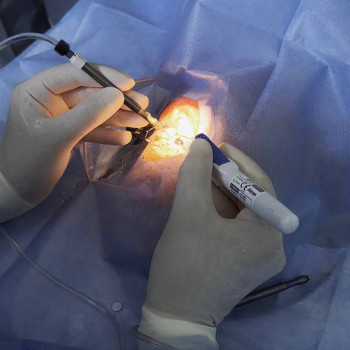

Аппаратное лечение зрения у ребенка в Кременчуге

- Лечение близорукости у ребенка

- Аппаратное лечение зрения у ребенка

- Лечение амблиопии у ребенка

- Коррекция косоглазия у ребенка

Сколько стоит аппаратное лечение зрения у ребенка в Кременчуге

| ✅ Офтальмологический центр Визиум | 270 грн |